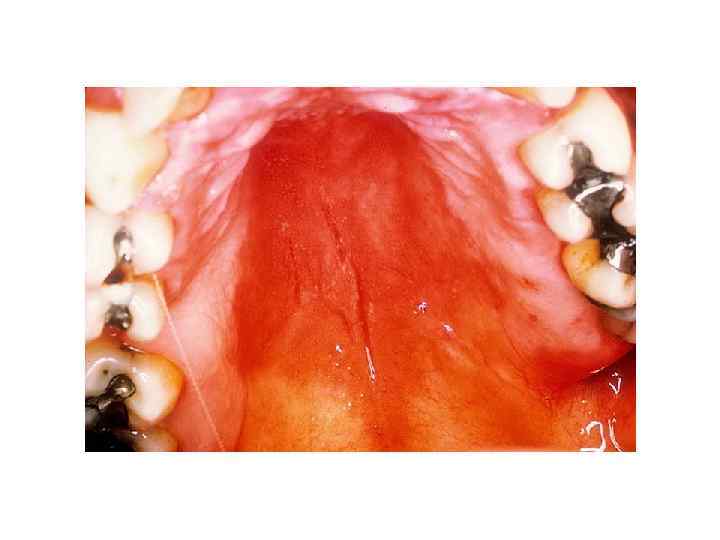

Созылмалы атрофиялаушы кандидоз Алмалы салмалы астындағы өзгерістер (қызару, құрғау, эрозиялану және папилломатоз); Екі езуде тіліктер пайда болуы (кандидоздық ауыздық); Тілдің үсті құрғақ, түсі таңқұрай жемісі түстес, бүртіктері атрофияға ұшырғандықтан беті жылтыр.

кандидоз Хронический атрофический